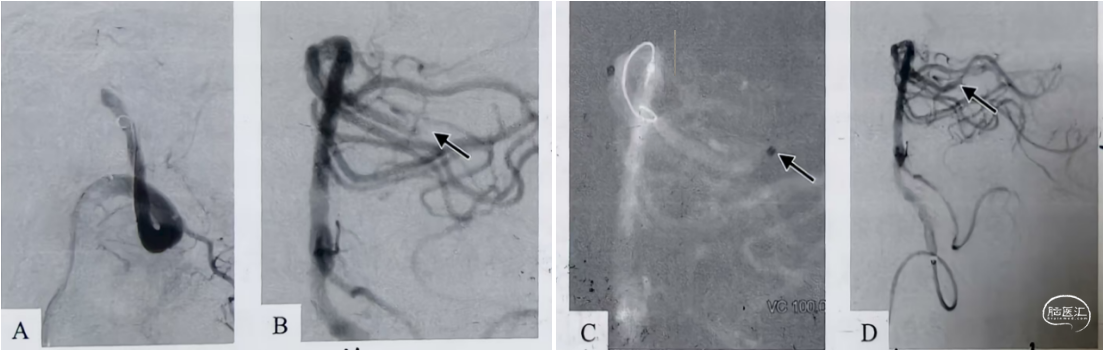

A、造影显示基底动脉尖闭塞 B、基底动脉抽吸取栓再通 ,但大脑后动脉P2段异位栓塞。C、0.029in微导管超选大脑后动脉闭塞段(箭头)超选取栓;D、造影显示微导管抽吸后血管再通(箭头)